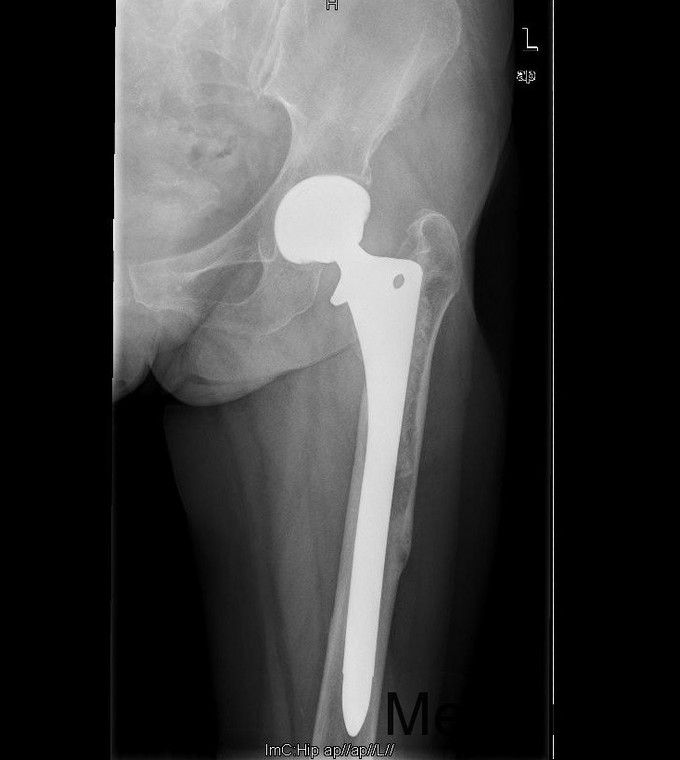

查体:专科:左髋部后外侧陈旧手术瘢痕,左髋关节前方压痛、无轴向叩击痛阴性,无大转子叩击痛,双下肢感觉及血运均正常。双下肢肌力V级。动量:右髋内外旋诱发疼痛,屈曲90度疼痛。外旋明显滚动试验阴性,左髋4字试验阳性。双下肢等长。左髋关节屈90°,伸0°,外展40°,内收20°,内旋30°外旋10°。右髋关节屈120°,伸直0°,外展40°,内收20°,内旋30°外旋30°。 辅助检查:2010-12-08 ESR 6.0mm/h,2011-01-04外院CRP8.5mg/l(参考范围0-10mg/l)X线示左双动股骨头置换术后,假体松动、下沉,髓腔内可见骨水泥影。近端干骺端骨质明显缺损。髓腔内侧皮质形态不规则。

诊断:左双动股骨头置换术后假体松动、下沉、股骨骨缺损(PaproskyII型) 治疗:患者在全麻下左双动股骨头假体取出+同种异体骨植骨+左全髋关节翻修术,术后予以抗炎(二联)+抗凝+镇痛+护胃+补液等治疗,并予以抗骨质疏松药物